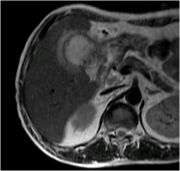

[黄色肉芽腫胆嚢炎] 手術:胆嚢摘出術(結腸切除術併施)

血液検査にて炎症反応の上昇を認め、精査の結果、急性胆嚢炎と診断。胆嚢摘出術(結腸切除術併施)を施行した。病理結果は黄色肉芽腫胆嚢炎であった。

MRI画像